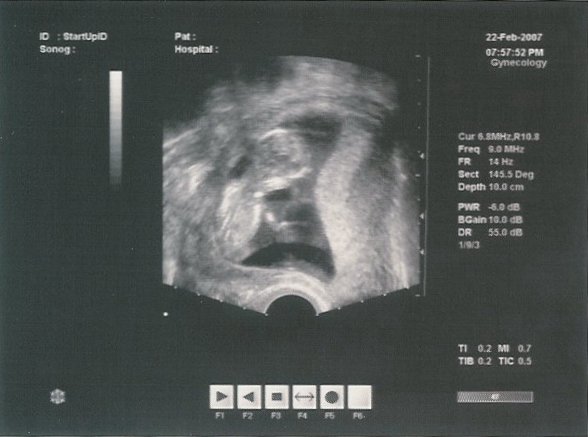

Ma voltam a másik dokinál...megnézte a bébit, és azt mondta minden ok, kora szerinti méretekkel rendelkezik.

Meg sem mutatta a képernyőn sem a babát...még szerencse,hogy úgy felejtette a monitort én meg gyorsan megnéztem.

Édes nagyon a picike.